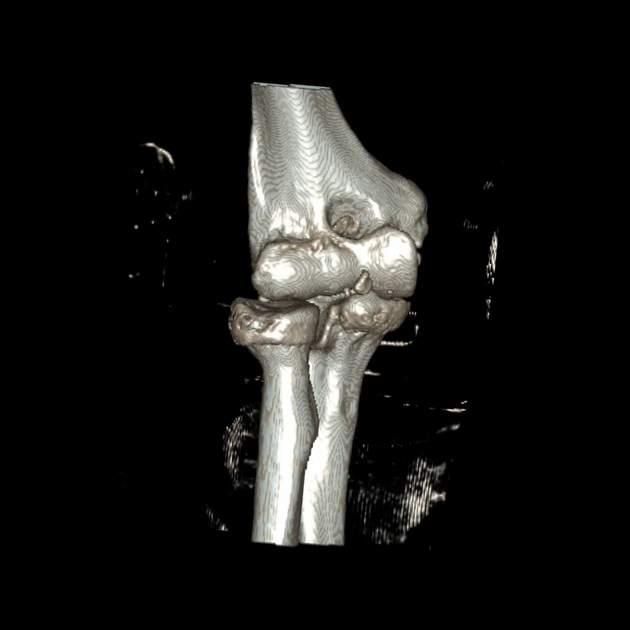

Mảnh vỡ trong khớp khuỷu (Intraarticular Bodies, Elbow)